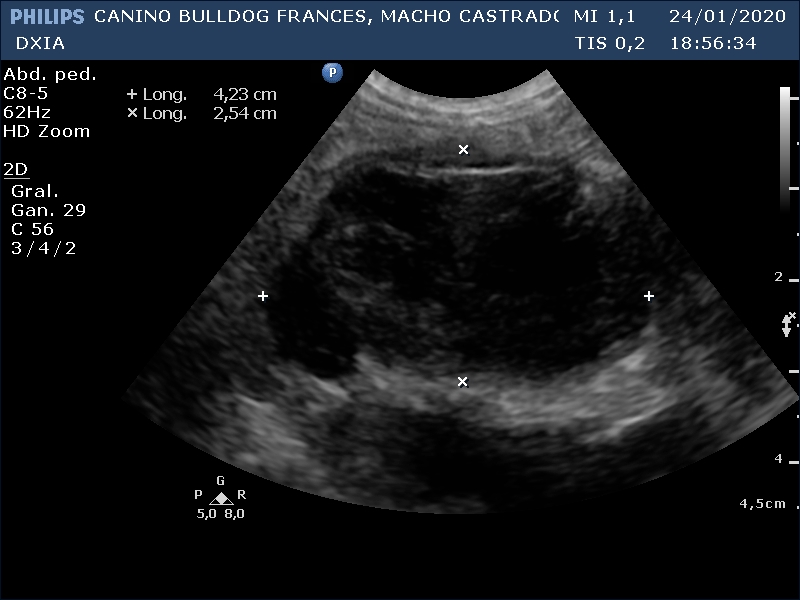

RONY

Del informe ecográfico de Rony se destaca la existencia de varias alteraciones:

Neoformación en la que se observa estructura en capas en su zona dorsal. Se realiza PAF ecoguiada.

En el caso de Rony se recomienda extirpar neoformación y realizar análisis anatomopatológico de esta. Valorar PAF/biopsia prostática debido a su heterogenicidad.